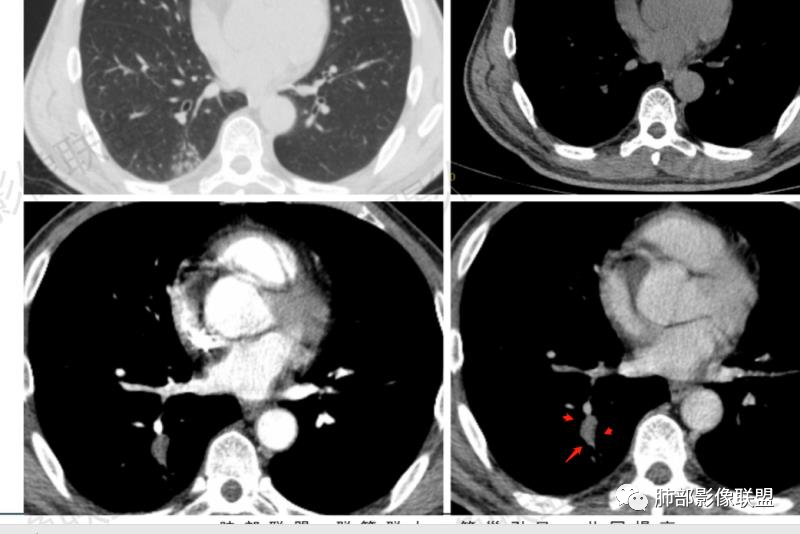

病理结果

病例小结

影像与临床:

1.中年男性,发现肺部结节增大就医(一年前发现肺部结节),缺乏临床表现。有糖尿病基础。

2.右肺下叶背段指尖大小结节影伴外围片状影及小结节影,片影中有结节感。

3.近背段支气管开口附近结节密度不甚均匀,未见钙化或脂质密度区。边界清楚光整,内侧平直,未见典型深分叶及毛刺,增强扫描轻度强化。

4.哌拉西林、左氧氟沙星等治疗一周后,较大结节影及外围病灶范围均见增大。

5.背段支气管于结节内侧份“旁现侧出”,管壁完整,管腔少量分泌物,近乎疏通状态。结节内隐约出现微小含气空腔。

6.肺门及纵隔未见增大淋巴结。

综合分析:

1.会是肺腺癌吗?较长时间段内固定存在的结节影我们会想到新生物。本例结节影边界清楚光整,内缘平直,缺乏典型深分叶及毛刺,未见异常强化,未见肿大淋巴结等,缺乏肺腺癌的依据。

2.会是硬化性肺细胞瘤吗?病灶支气管相关,未见异常强化,短期内增大等几乎完全将硬化性肺细胞瘤排除在外。

3.同样的理由也不支持错构瘤,尽管结节影密度不均匀。我们几乎不可能在错构瘤中观察到如此穿行的支气管!

4.会是隐球菌感染吗?急性感染,如易形成空洞的肺炎克雷伯杆菌感染等我们自然不在考虑之列,无论是临床表现还是影像学改变。肺部隐球菌病灶有时酷似新生物,但如此漫长不出新花样的侵袭性病灶则非常罕见!

5.临床表现轻微的病灶还有肺结核!可以长期“默默无闻”。本例结节影密度欠均匀,强化不显著,可以出现小空洞,周围见小结节影等,结核确实存在众多支持点。

不事张扬的小空洞,最常见的还是结核!

6.外围片影的迅速扩大应考虑为继发性改变,不宜单以结核感染本身加以解释。